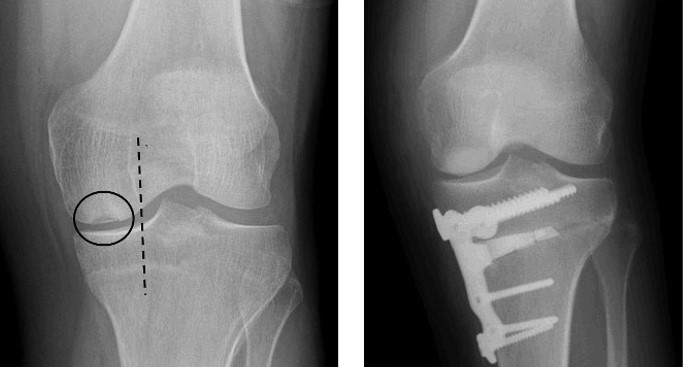

Knee osteotomy surgery requires precise realignment of the knee bones to correct deformities and restore proper joint function. Traditional planning using 2D X-rays and manual measurements is time-consuming, prone to error, and struggles to account for patient-specific anatomy, creating a gap in achieving consistently accurate surgical outcomes. There is a growing need for AI-powered tools that provide surgeons with precise, intuitive, and actionable virtual models to improve decision-making and surgical accuracy.

Our goal is to leverage AI to enhance Planning Logic’s surgical planning platform. Specifically, the team is developing AI-driven tools and models that generate accurate 3D virtual representations of knee anatomy, assist in pre-surgical planning, and provide predictive insights for better surgical outcomes.